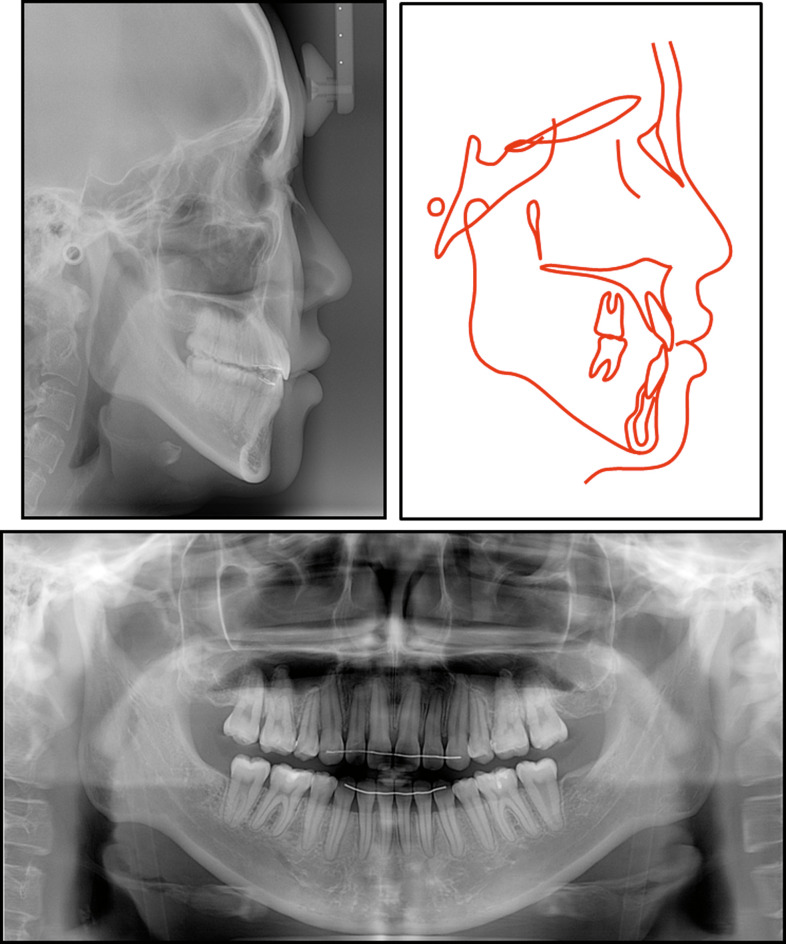

The panoramic radiograph showed no pathology (Figure 2). The lateral cephalometric analysis indicated a skeletal Class II (ANB, 3.5°) with retruded mandible (N per to Pog, −4.5 mm), and hyperdivergent vertical pattern (PFH/AFH, 59.5%; MP-FH, 32.7°). The maxillary incisors were slightly proclined and the inclination of the mandibular incisors was within the normal range (U1 to FH, 120.7°; IMPA, 90.0°). Vertical maxillary excess was evident in both the anterior and posterior dentition (U1-PP, 36.9 mm; U6-PP, 27.9 mm). Maxillary central incisor exposure at rest was relatively excessive (U1 to stomion, 4.8 mm). The occlusal plane angle was within the normal range (OP to FH, 12.8°). In addition, the mandibular vertical height was also longer than normal (L1 to mandibular plane, 47.7 mm; L6 to mandibular plane, 37.0 mm; Table 1).

Figure 2.

Pretreatment records: lateral cephalogram, cephalometric tracing, and panoramic radiograph.